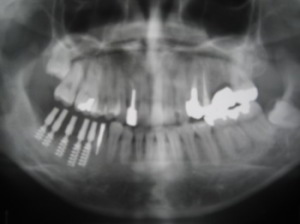

47番が歯根破折

1998/12/03

割れて痛い歯を抜歯。

1999/05/13